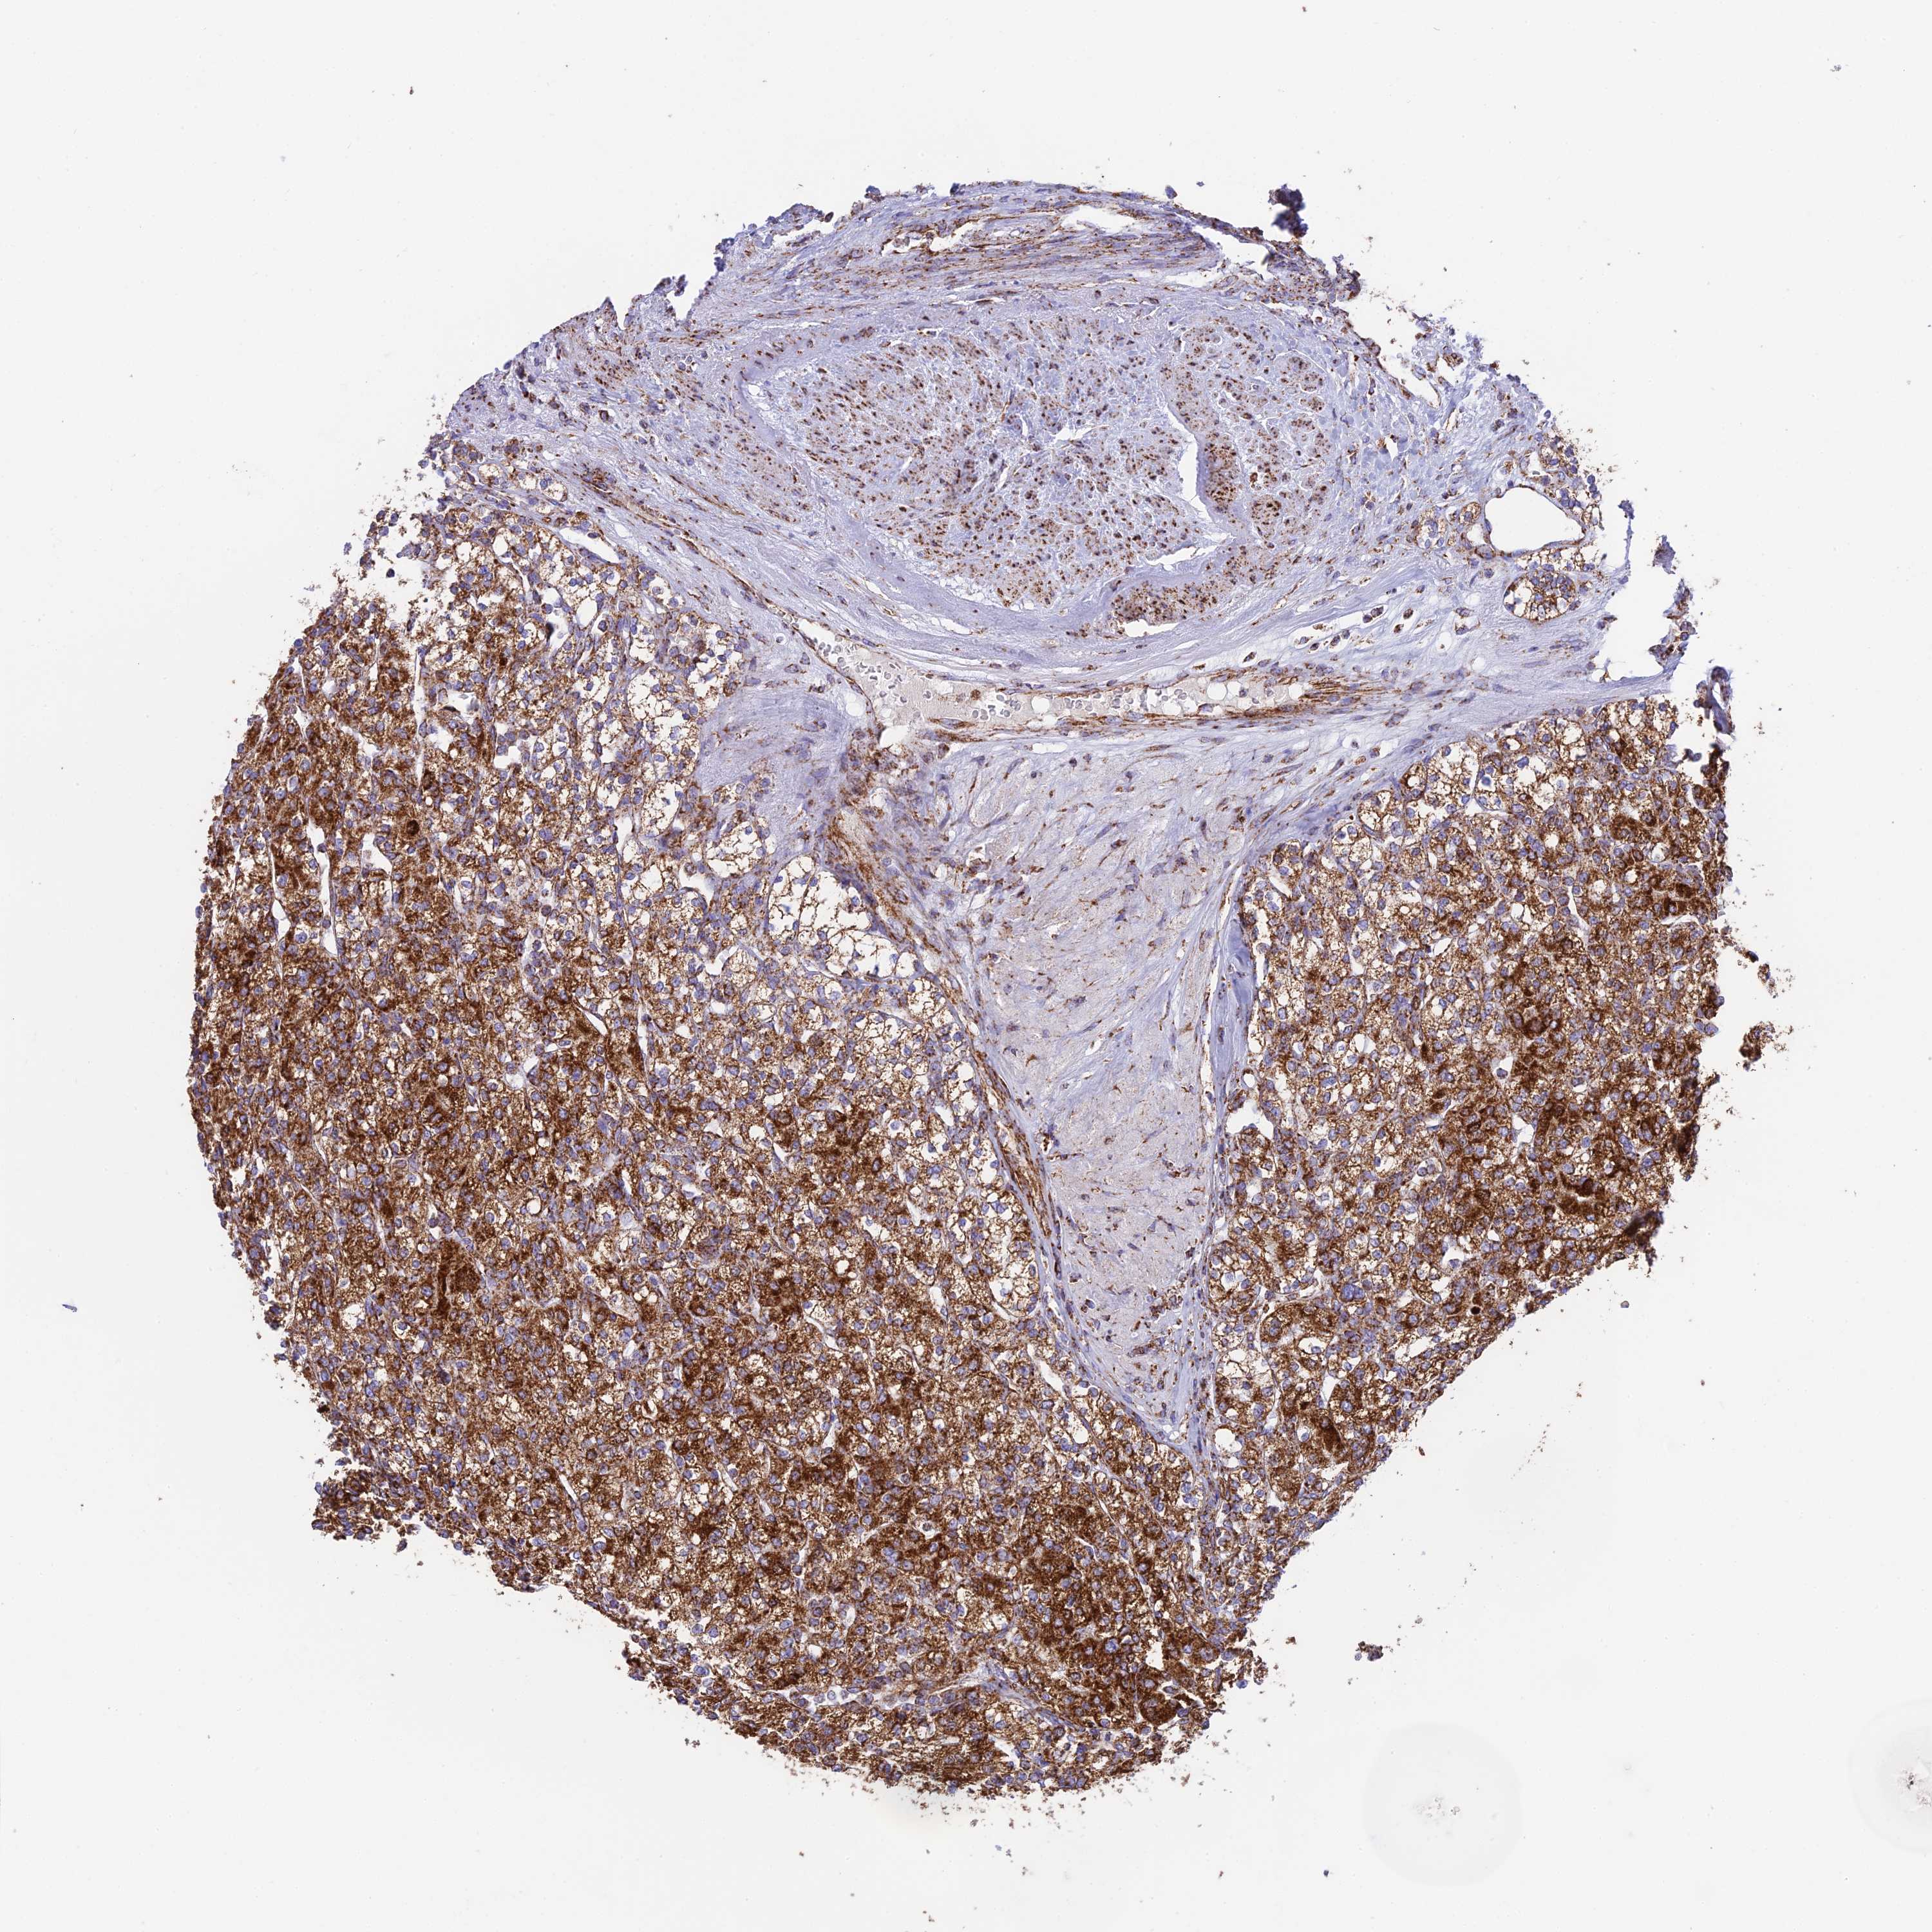

KIDNEY RENAL PAPILLARY CELL CARCINOMA (TCGA) - Interactive survival scatter ploti

The Survival Scatter plot shows the clinical status (i.e. dead or alive) for all individuals in the patient cohort, based on the same data that underlies the corresponding Kaplan-Meier plots. Patients that are alive at last time for follow-up are shown in blue and patients who have died during the study are shown in red.

The x-axis shows the expression levels (FPKM) of the investigated gene in the tumor tissue at the time of diagnosis. The y-axis shows the follow-up time after diagnosis (years). Both axes are complimented with kernel density curves demonstrating the data density over the axes. The top density plot shows the expression levels (FPKM) distribution among dead (red) and alive patients (blue). The right density plot shows the data density of the survived years of dead patients with high and low expression levels respectively, stratified using the cutoff indicated by the vertical dashed line through the Survival Scatter plot. This cutoff is automatically defined based on the FPKM cutoff that minimizes the p-score. The cutoff can be changed by dragging the vertical line or by entering a cutoff value in the square labeled "Current cut-off".

Under the Survival Scatter plot the p-score landscape (black curve; left axis) is shown together with dead median separation (red curve; right axis). Dead median separation is the difference in median mRNA expression between patients who have died with high and low expression, respectively. It is calculated as follows: median FPKM expression of dead patients with high expression - median FPKM expression of dead patients with low expression. This is intended to aid the user in visually exploring custom cutoffs and the associated p-scores and dead median separation.

Individual patient data is displayed and can be filtered by clicking on one or more of the category buttons on the top of the page. Categories describing expression level and patient information include: high, low, alive, dead, female, male and tumor stages. The scale of the x-axis can be toggled between linear and log-scale by clicking on the "x log" button. Mouse-over function shows TCGA ID, patient information and mRNA expression (FPKM) for each patient.

& Survival analysisi

Kaplan-Meier plots summarize results from analysis of correlation between mRNA expression level and patient survival. Patients were divided based on level of expression into one of the two groups "low" (under cut off) or "high" (over cut off). X-axis shows time for survival (years) and y-axis shows the probability of survival, where 1.0 corresponds to 100 percent.

CHCHD3 is not prognostic in Kidney Renal Papillary Cell Carcinoma (TCGA)